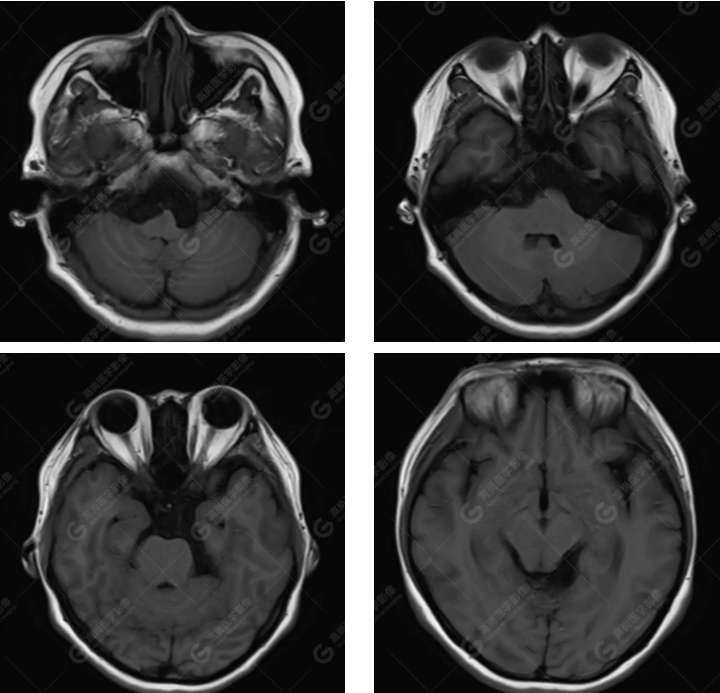

MRI 影像所见:

延髓池、桥前池、双侧桥小脑角区、鞍上池至左侧小脑幕下见团片状异常信号影,呈长 T1 长 T2 信号,FLAIR 序列呈不均匀稍低信号,DWI 序列呈高信号,ADC 图低信号,增强后无强化。右侧面听神经受压向后移位,双侧三叉神经及左侧面听神经被包埋,显示不清。

延髓池、桥前池、双侧桥小脑角区、鞍上池至左侧小脑幕下胆脂瘤,右侧面听神经受压向后移位,双侧三叉神经及左侧面听神经被包埋